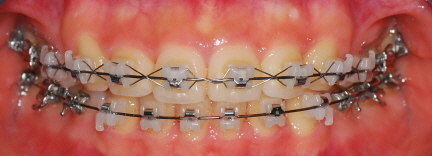

치과에 다녀왔습니다. 벌써 25번째 치아교정후기네요ㅎㅎㅎ 먼저 치아 사진을 보시면 아랫니에 공간이 살짝 생긴 것이 보이는 데요

<정면 사진>

<하악사진> 저는 처음에 왜 다시 벌어지지? 하고 걱정했는데 치과선생님께서 벌리는 것이 더 어렵다고 하셨어요~ 의도된 과정이었더라구요*^^* 이번달은 고무줄을 다시! 이용하여 윗니는 뒤로 아랫니는 앞으로 당겨주는 작업을 할거에요 그래서 고무줄은 위아래로 걸게 되었습니다~ 밥먹을 때 마다 뺏다 꼈다 해야 하는데 오랜만에 다시 고무줄끼니 정말....아프네요 맛잇는거 있어도 못먹고.. 옛날에 엄마가 치아가 많이 빠져서 딱딱한거 먹는 저랑 동생들 보면서 밥먹을때마다 부럽다고 하셨었는데 지금 제가 그러니 진짜 부럽고.. 엄마께 미안한 마음도 들고 그래요..ㅠㅠ

아아 쨋든 이번달 과정은 고무줄이구요 한가지 더~ 윗니가 예전사진을 보면 앞니 뒤가 많이 울퉁불퉁 한 것을 볼 수 있는데요 윗니와 아랫니가 서로 좀 더 가깝게 하기 위해 뒷부분을 좀 깎는 작업을 했습니다 치과쌤의 표현 방식을 빌리면 일종의 배가 나온 부분을 다이어트 시켰다고나 할까요?!ㅎㅎㅎㅎ (내 배도좀 해야될듯....)